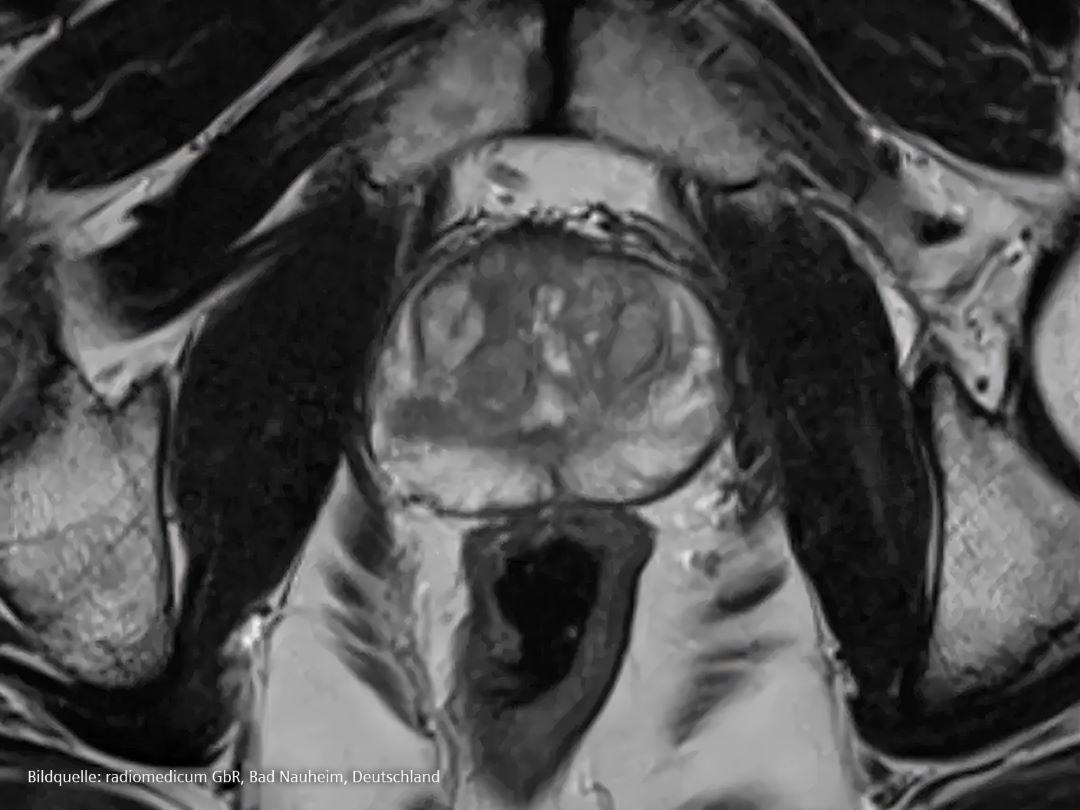

Diagnose und Staging

Was passiert, wenn Ärzt*innen vermuten, dass ein Patient Prostatakrebs haben könnte?

Für eine Diagnose wird der Patient nach den oben beschriebenen Symptomen und nach möglichen Risikofaktoren einschließlich seiner Familiengeschichte befragt. Im Falle eines Verdachts können Ärzt*innen einige Tests anordnen.